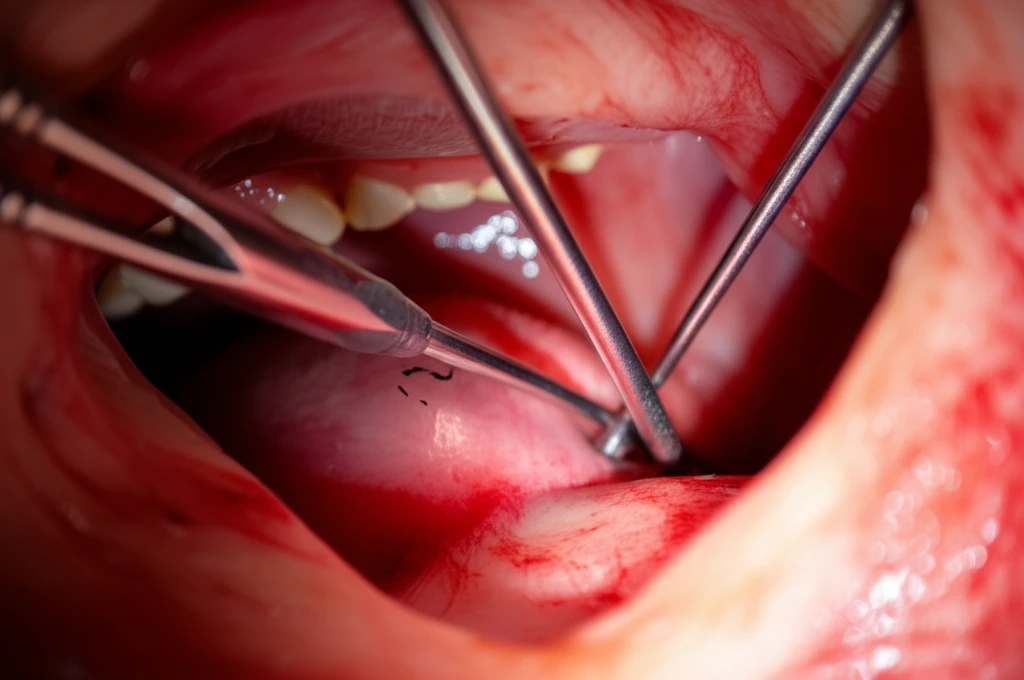

축농증 수술은 주로 내시경 부비동 수술로 진행됩니다. 얇은 내시경을 콧속에 넣어 부비동 입구를 넓히고, 염증 조직이나 물혹 등을 제거하는 방법이죠.

- 내시경 삽입: 콧속에 내시경과 필요한 수술 도구를 넣습니다.

- 병변 제거: 내시경을 통해 부비동 내부를 자세히 보면서 염증 조직과 물혹 등을 깨끗하게 제거합니다.

- 부비동 입구 확장: 좁아진 부비동 입구를 넓혀 원활한 공기 흐름과 분비물 배출을 돕습니다.